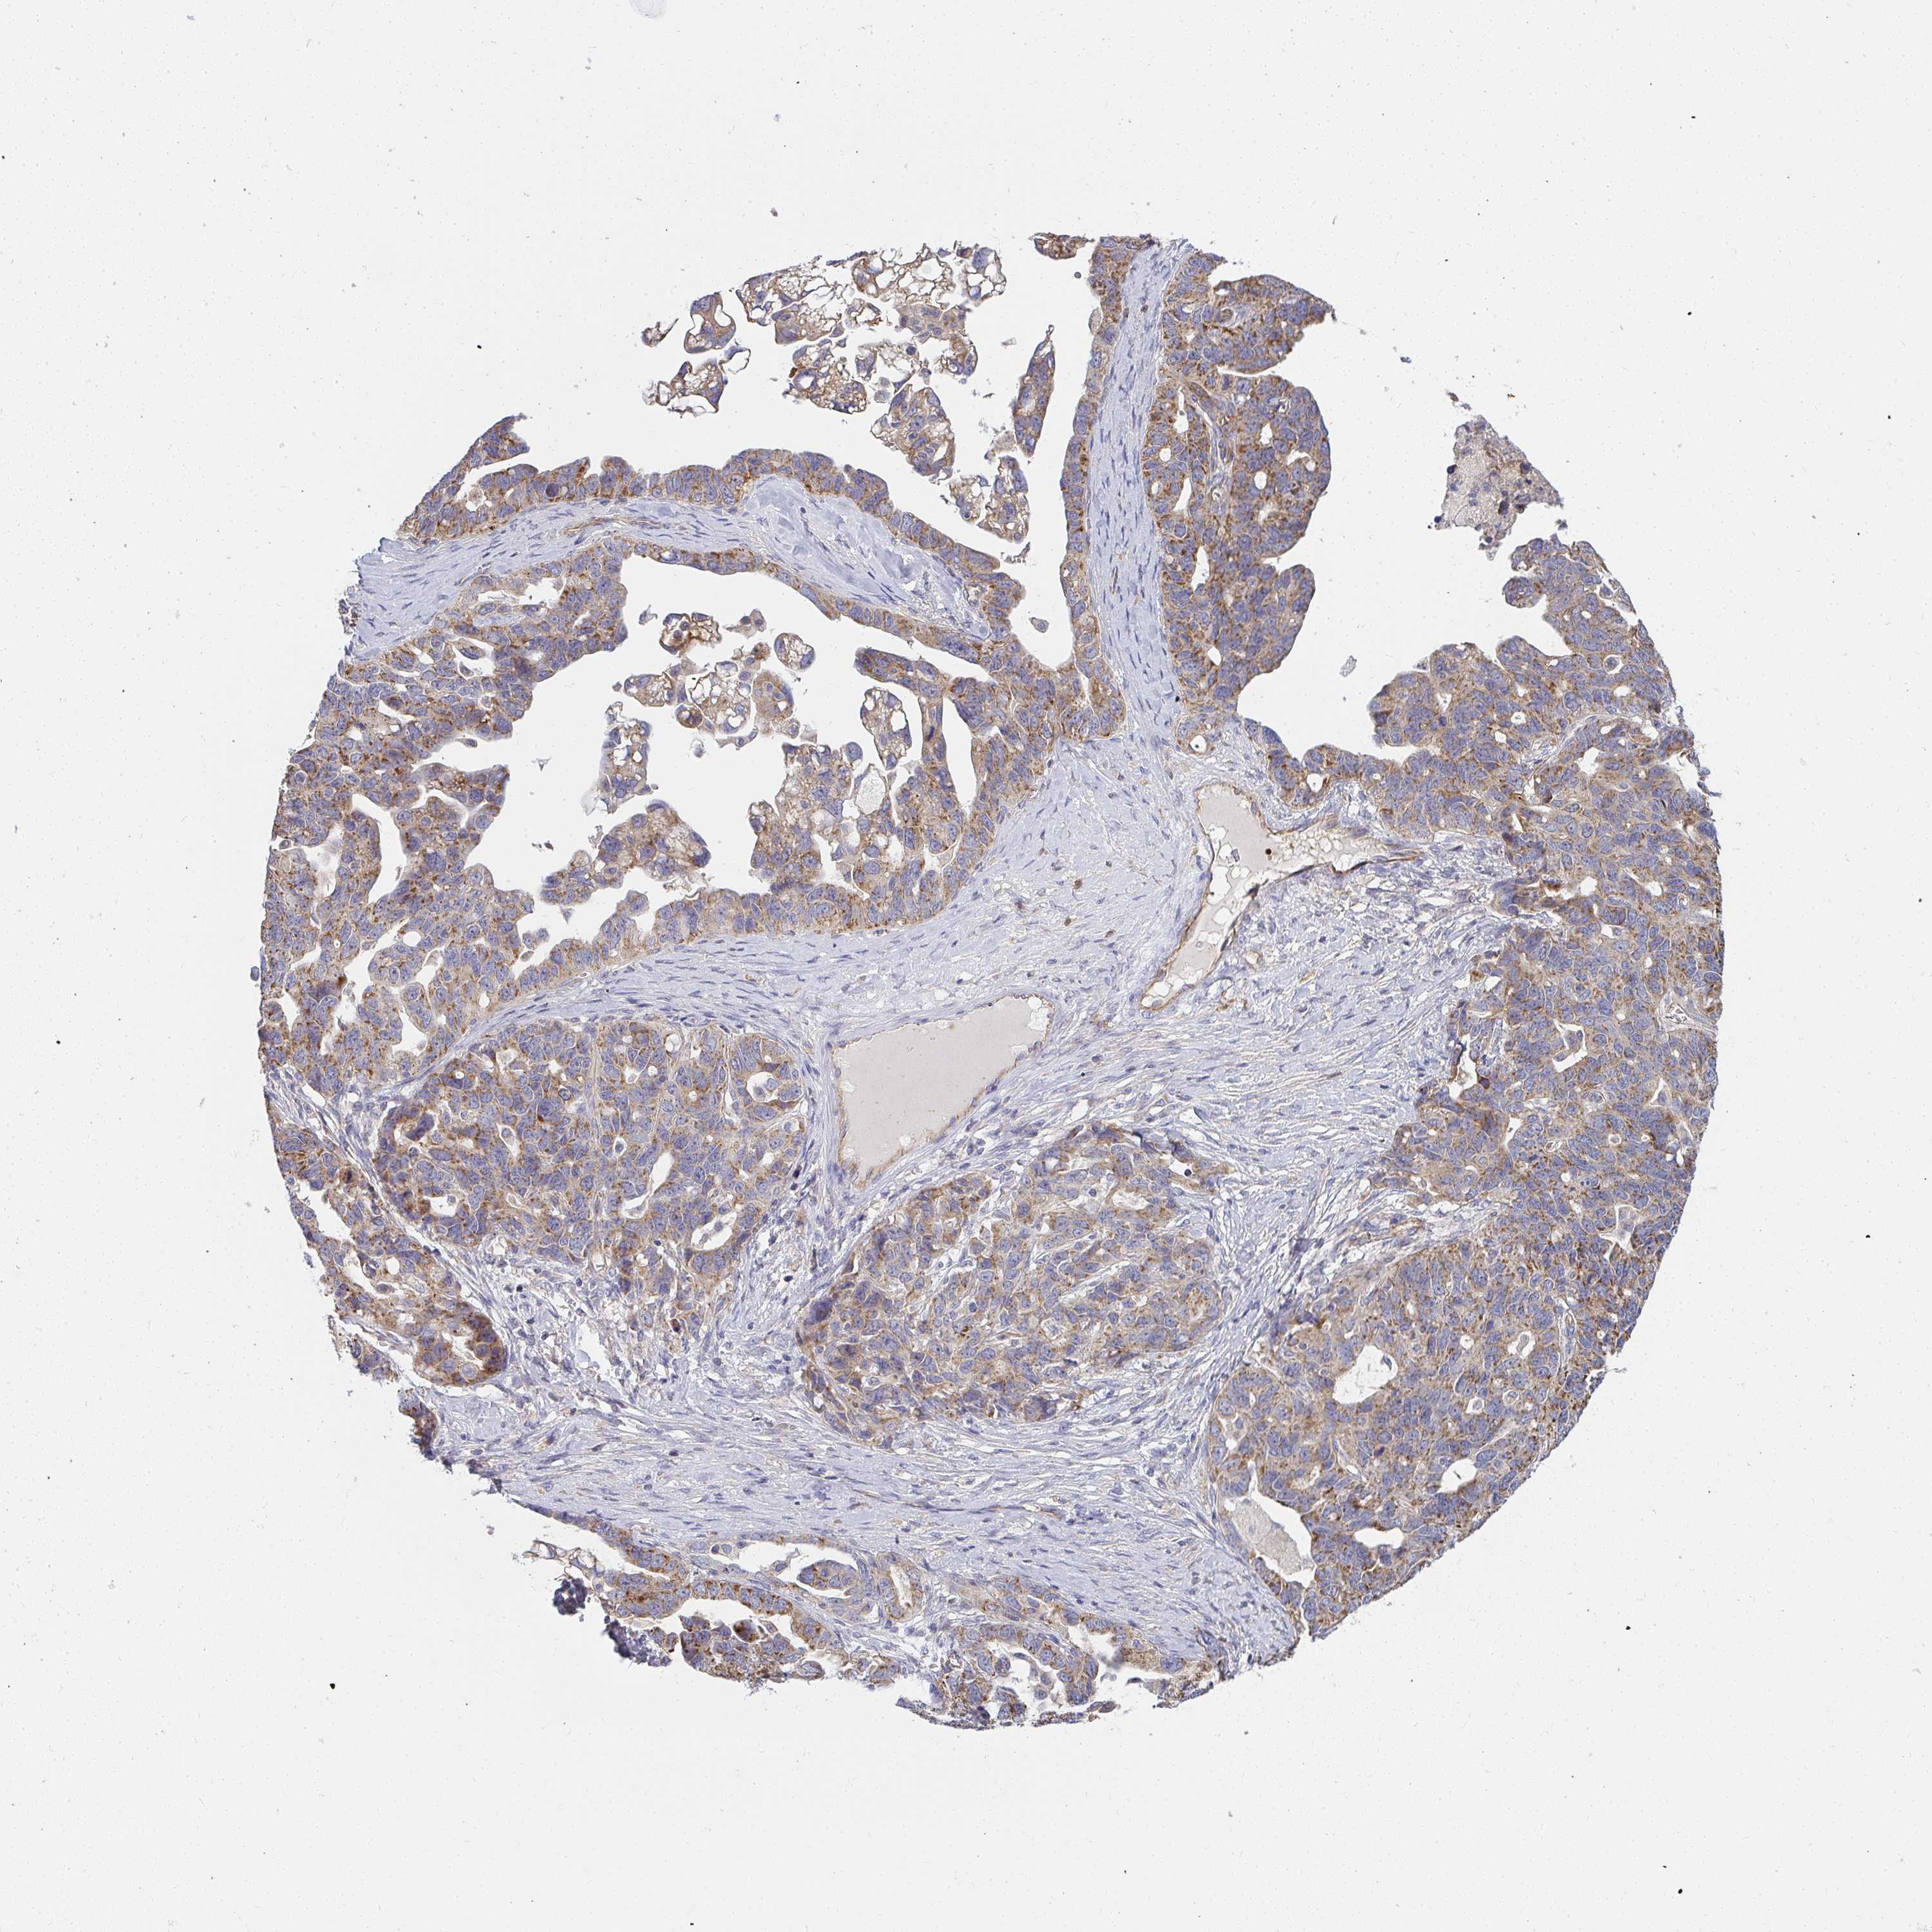

OVARIAN CANCER - Protein expressioni

A mouse-over function shows sample information and annotation data. Click on an image to view it in a full screen mode. Samples can be filtered based on level of antibody staining by selecting one or several of the following categories: high, medium, low and not detected. The assay and annotation is described here.

Note that samples used for immunohistochemistry by the Human Protein Atlas do not correspond to samples in the TCGA dataset.

Antibody stainingi

Antibody staining in the annotated cell types in the current human tissue is reported as not detected, low, medium, or high, based on conventional immunohistochemistry profiling in selected tissues. This score is based on the combination of the staining intensity and fraction of stained cells.

Each image is clickable and will lead to virtual microscopy that enables deeper exploration of all samples and also displays staining intensity scores, fraction scores and subcellular localization as well as patient and tissue information for each sample.

Antibody HPA058284

Antibody CAB020701

Carcinoma, endometroid